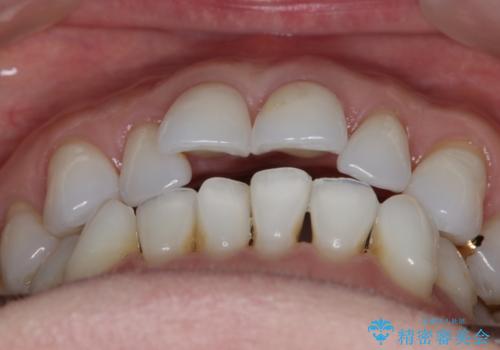

- 歯ぎしりや食いしばり、噛み合わせの治療とガタつきを治したいとのことでご来院されました。

検査の結果、前歯と臼歯の高さに差があり、前歯が全く当たらない状態になっているため歯ぎしりによって奥歯が削れてしまっているという状態でした。

マウスピースの矯正装置を用い、ガタつきを治しつつ奥歯を沈めていくことで噛み合わせ全体の改善を図りました。

オープンバイト

噛み合わせや筋機能など様々な原因で前歯の噛み合わせが大きく開いている状態を開咬(オープンバイト)といいます。

原因の除去や歯牙の移動で噛み合わせの治療を行うことで改善できる場合があります。